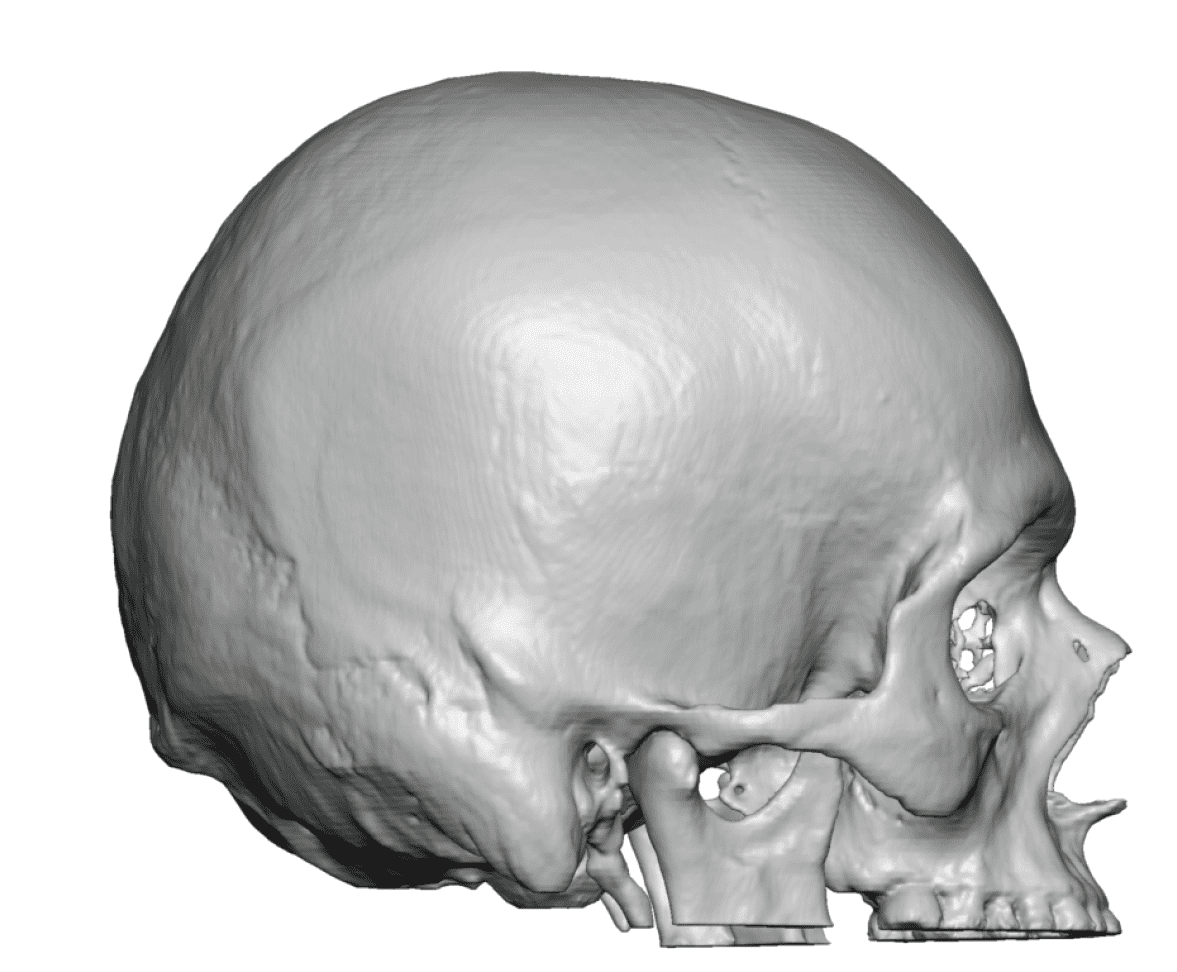

Desire to build up the flatter upper part of the back of his head.

Upper occipital skull augmentation using a custom skull implant.

Desire to build up the flatter upper part of the back of his head.

Upper occipital skull augmentation using a custom skull implant.